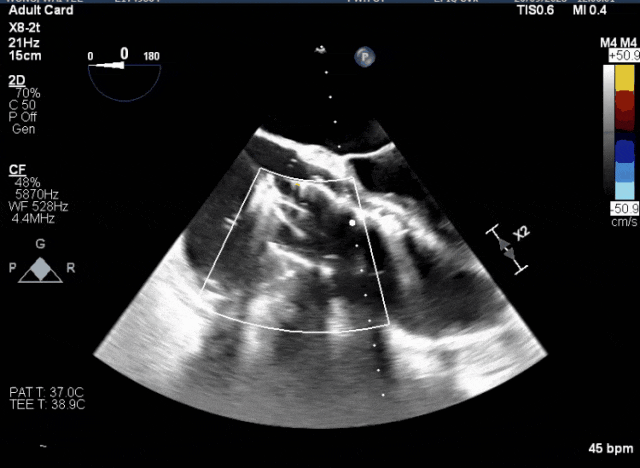

術(shù)前超聲顯示三尖瓣重度反流合并拴系

術(shù)中TEE成像困難,偽影干擾